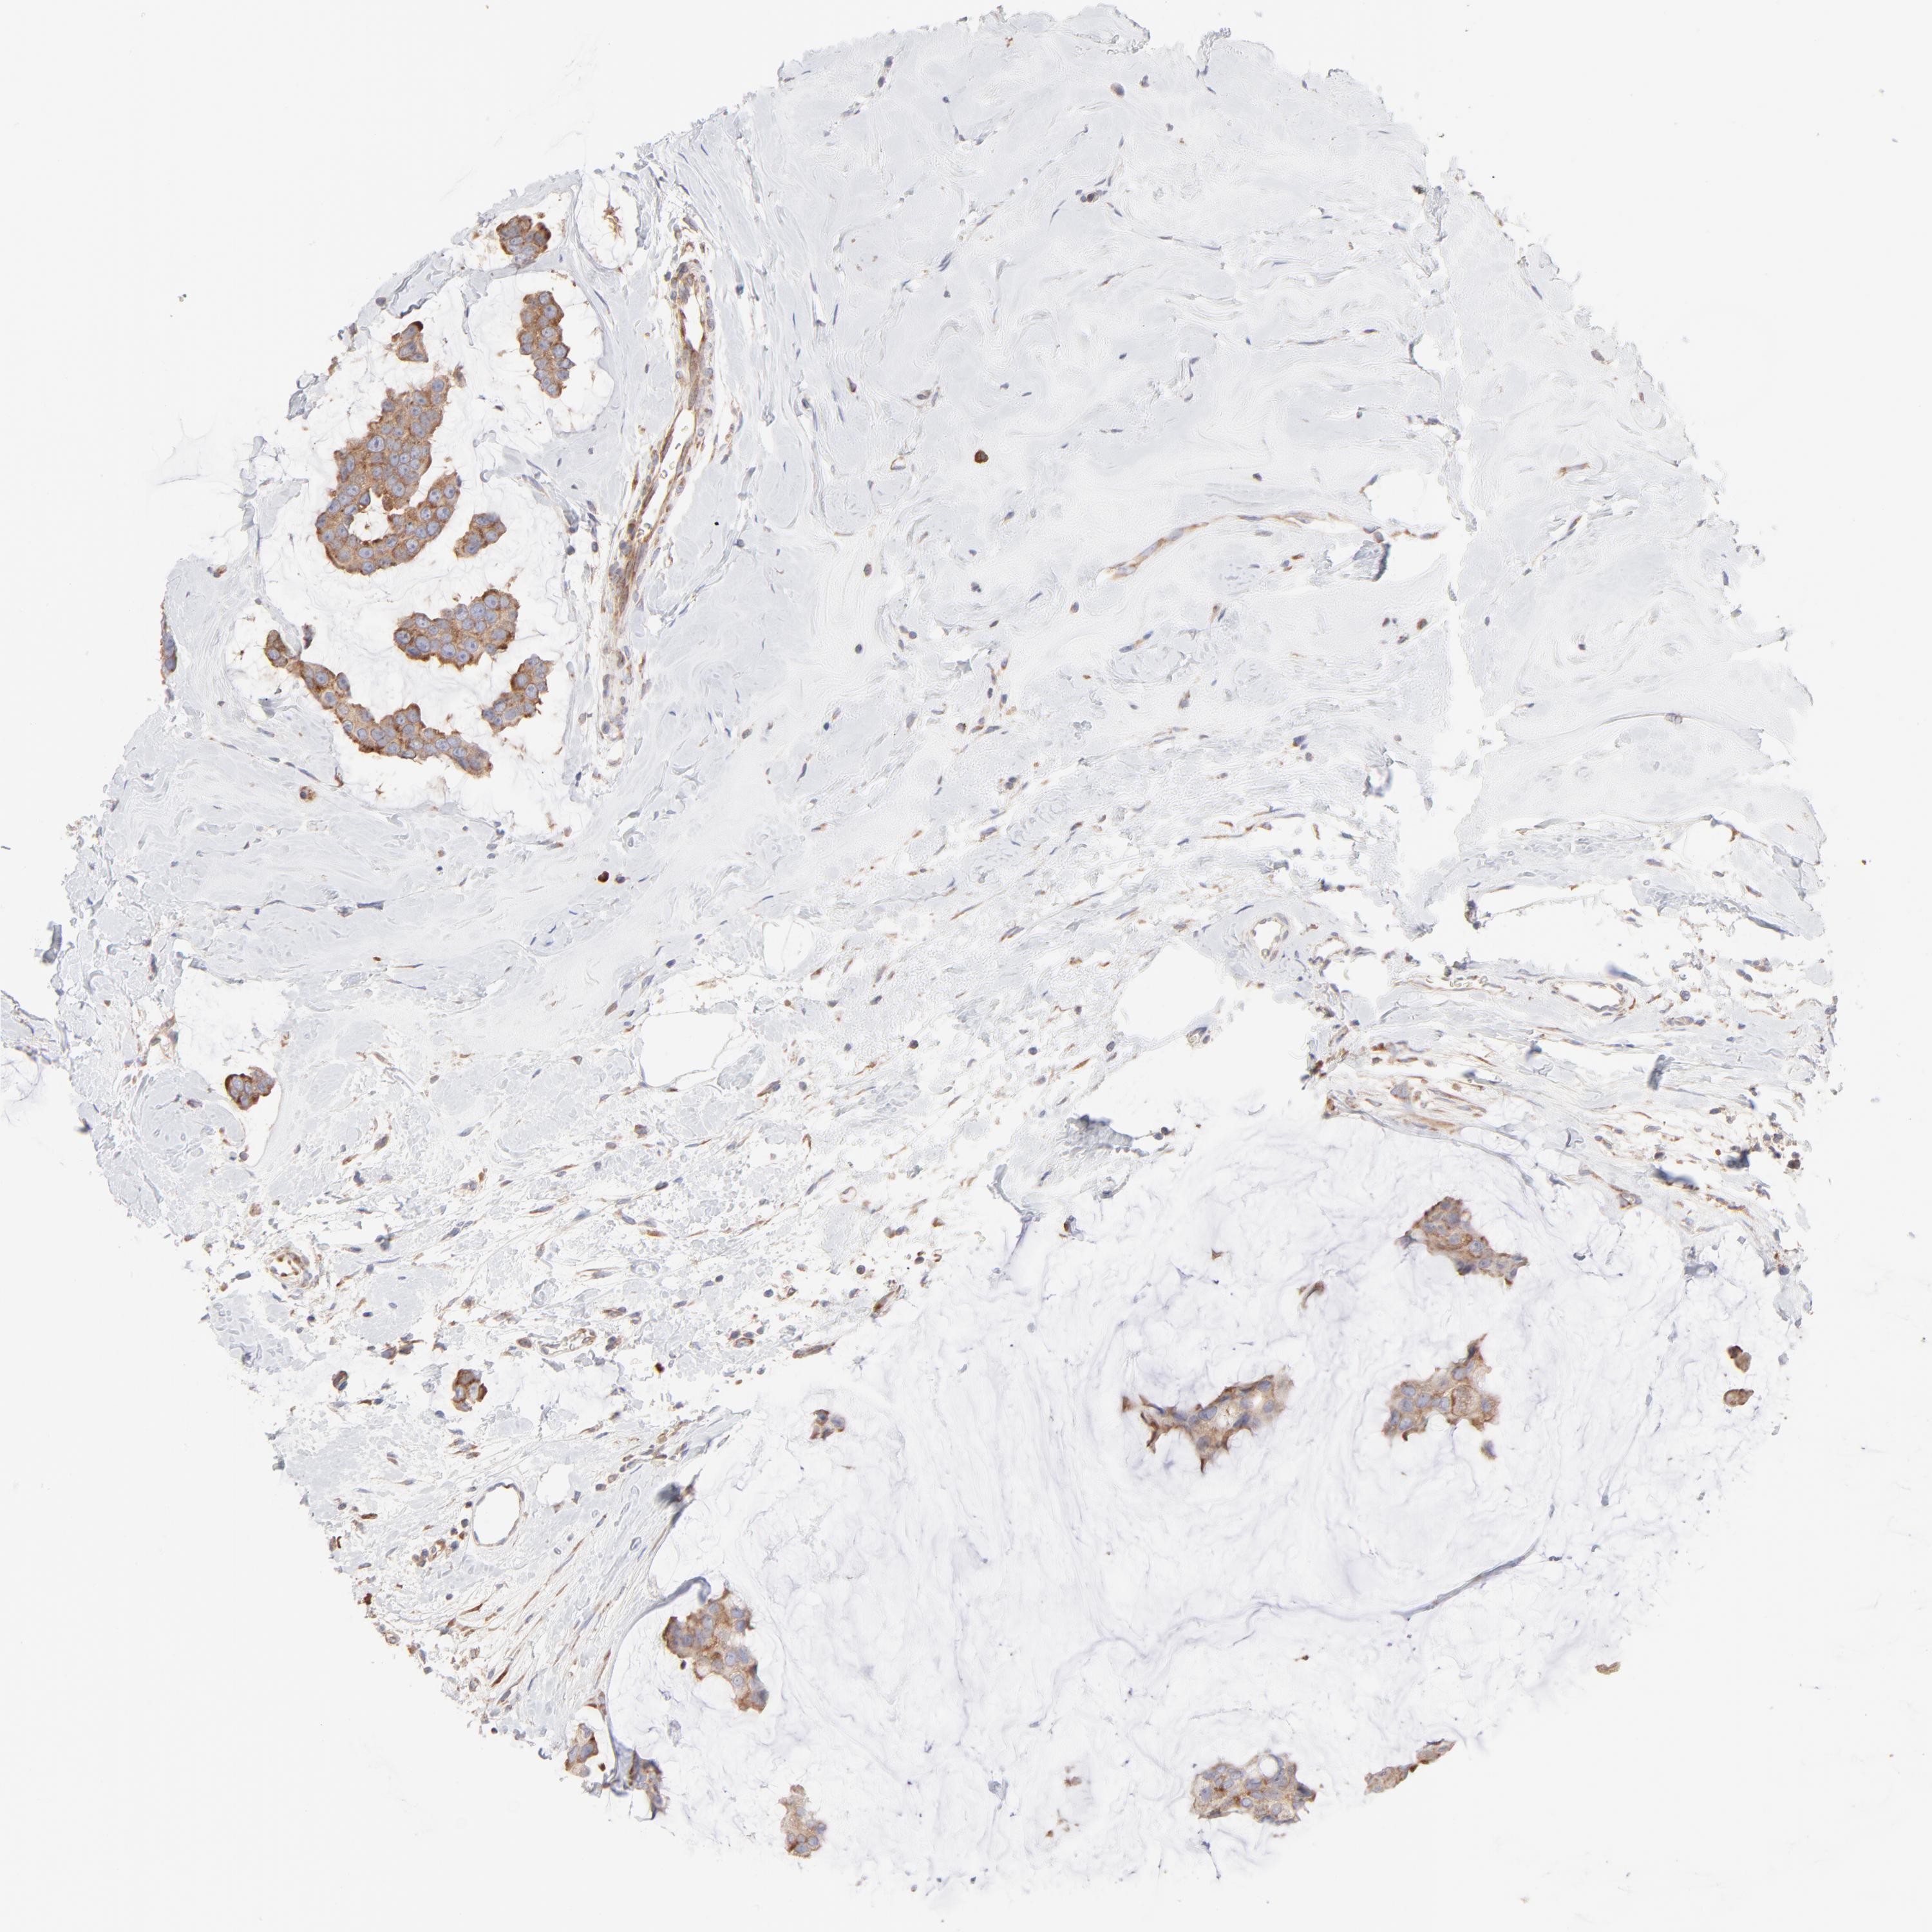

CANCER BREAST CANCER Show tissue menu

BRCA TCGA BRCA VALIDATION PROTEIN EXPRESSION

Breast cancer

Human cancer